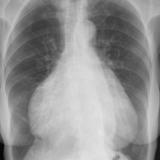

Cardiomegaly, esp RA PA

Date: 01/26/2009

Views: 2921

Cardiomegaly, esp RA Lat

Views: 3037